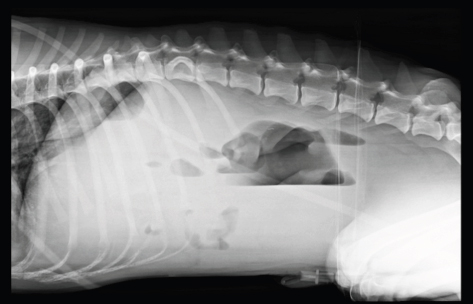

Interestingly, in one case diagnosed without mechanical gastrointestinal ileus, all the reviewers classified it wrongly as mechanical ileus when evaluating the VB views and correctly with only the HB view (Fig. 1).

Fig. 1. (A) Right lateral; (B) ventrodorsal; (C) left lateral; and (D) left-to-right lateral HB views of the abdomen of a dog presented with acute vomiting. In this case, the patient was correctly diagnosed as without mechanical ileus with the HB view and incorrectly diagnosed as mechanical ileus with the VB view by all reviewers. Abdominal ultrasound was unremarkable.